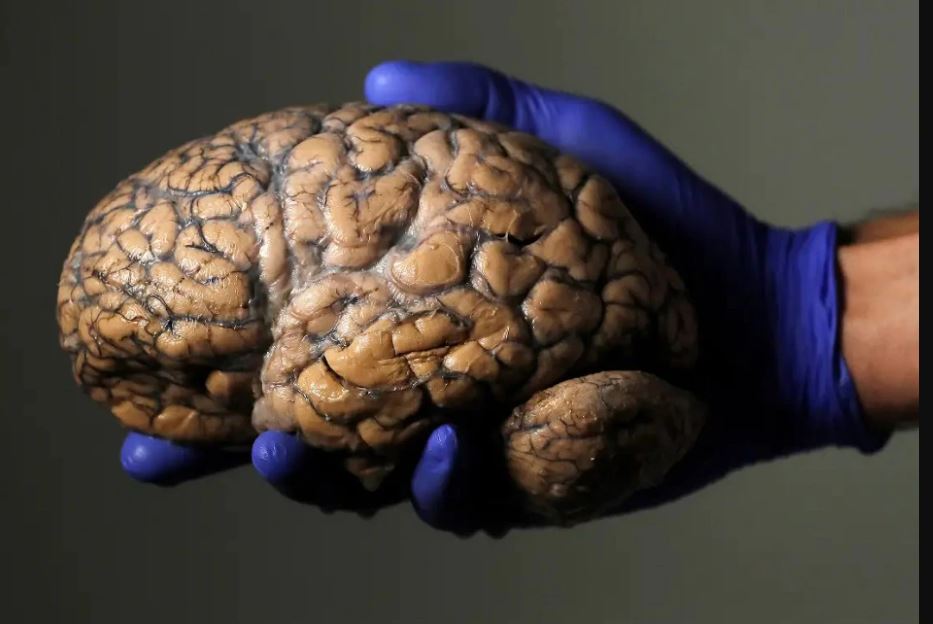

दिमागमा असर – ५० वर्षको उमेरमा मस्तिष्कको कार्य बढ्छ। यधपी ५५ को आसपासमा दिमागमा तनावको कारण बिस्तारै स्मृति कमजोर हुन थाल्छ। साथै स्मृति वा याद वृद्धि गर्न मेडिटेरेनियन डाइट अपनाउनुपर्ने हुन्छ। यसमा फलफुल, तरकारी, सम्पूर्ण अन्नहरू र स्वस्थ गेडागुडी पर्छन् ।